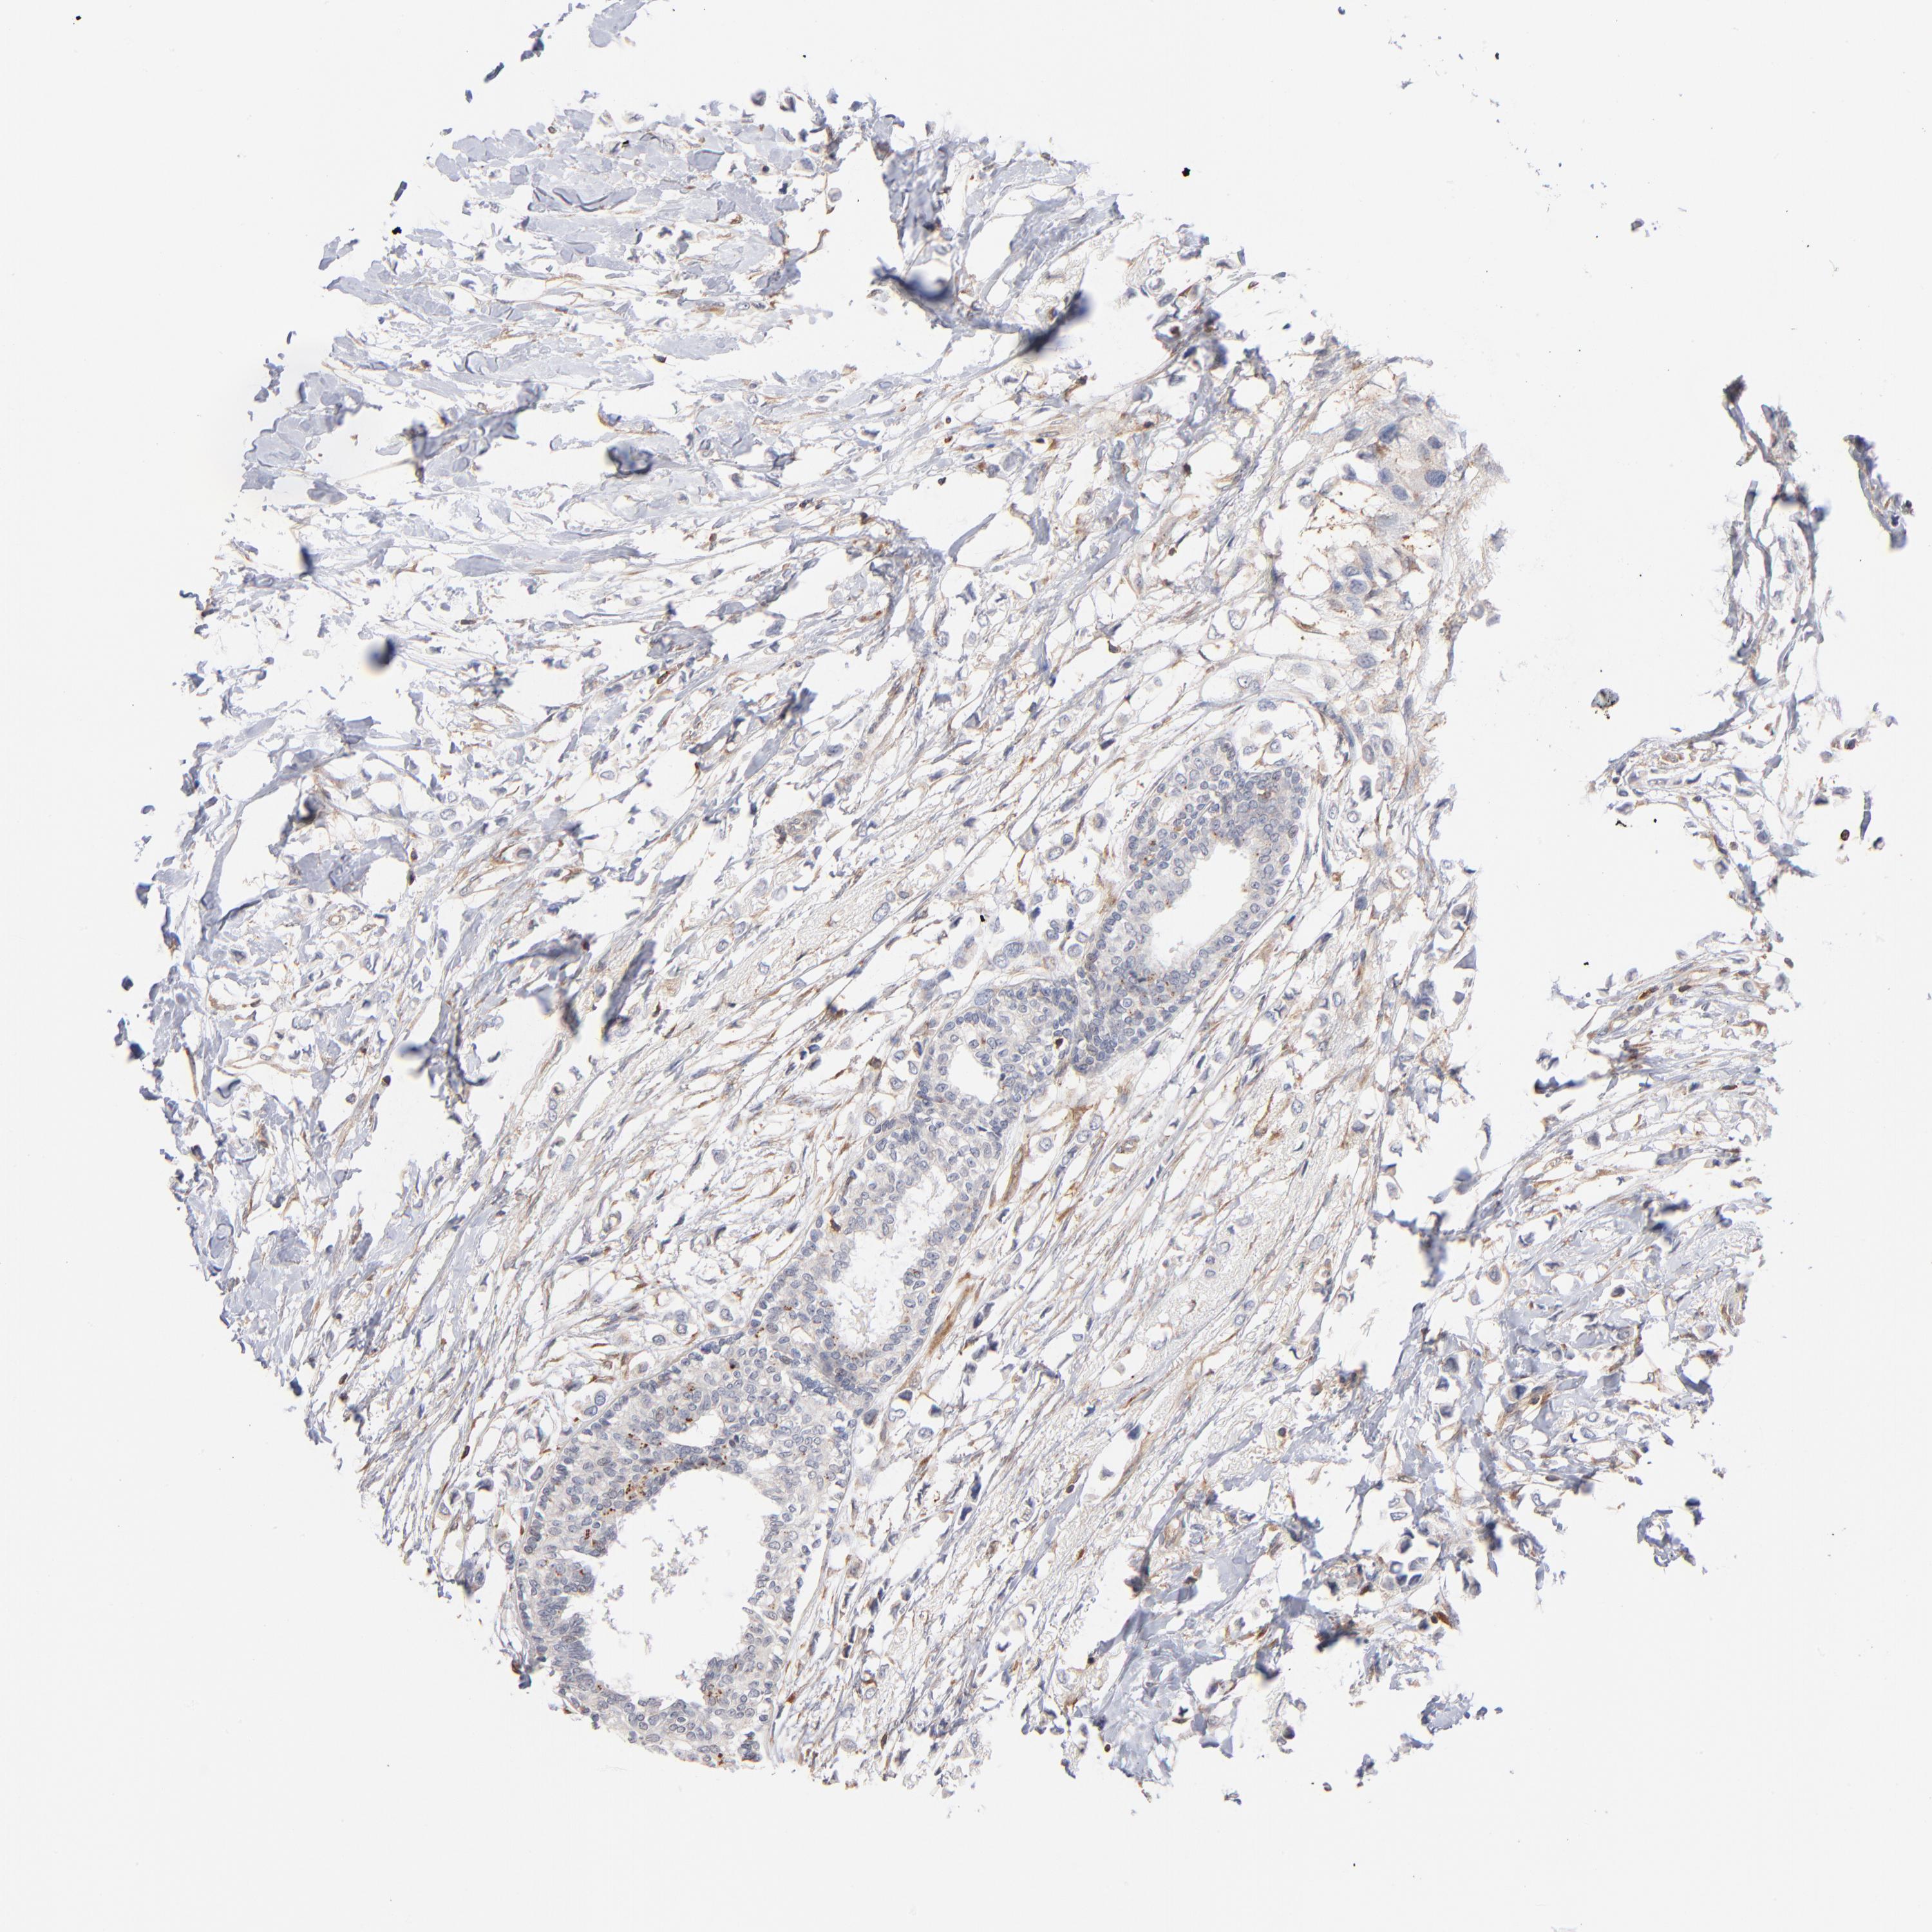

BRCA TCGA BRCA VALIDATION PROTEIN EXPRESSION

ANTIBODIES

AND

VALIDATION